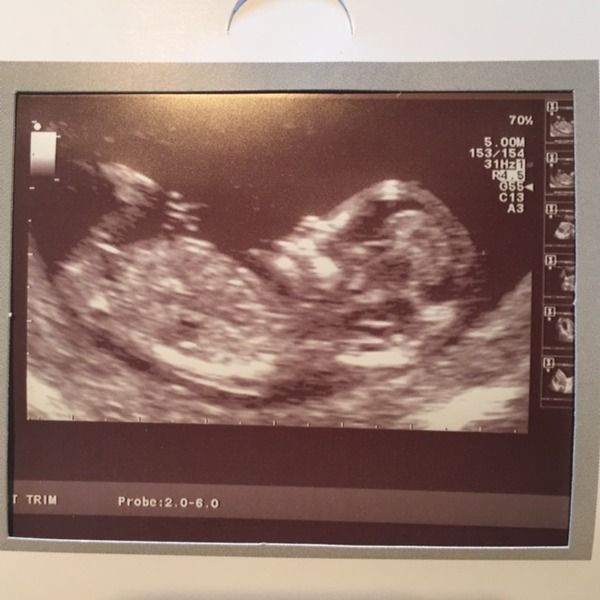

I had my 12 week scan yesterday and was also measured at 12 + 5 laughingGnomette :D this is our first baby and we were both amazed and in awe of the tiny human! Just wish I could of had more chance to watch the screen like my partner did :P

June 2016 #4 - 12 week scans, seeing tiny feet and hands!